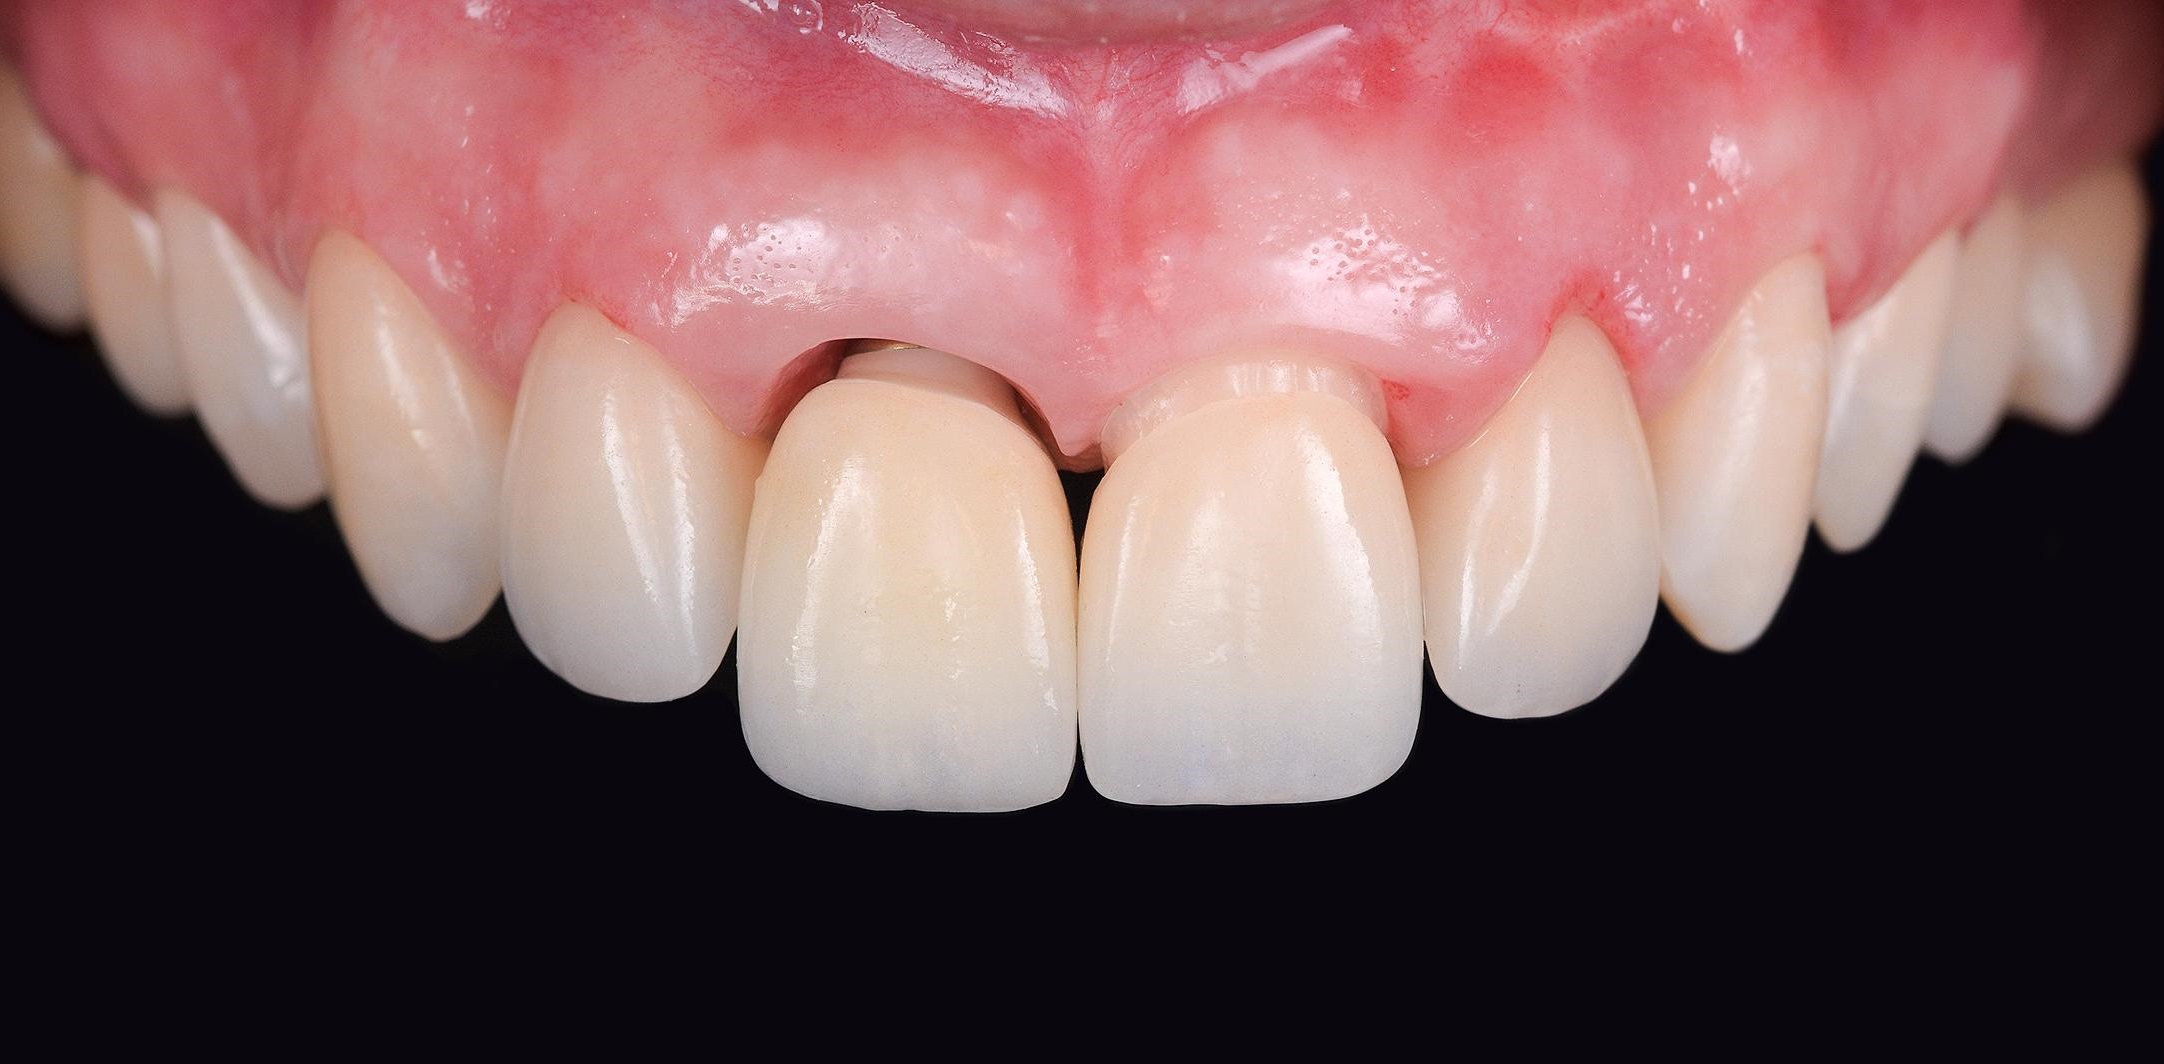

Ưu điểm thẩm mỹ thứ nhất: Thẩm mỹ lợi và mô nha chu đẹp nhất.

Việc sử dụng Healing Customized để tạo hình và tái lập mô nha chu, sử dụng Customzied Abutment để định hình giúp răng implant có nhân hóa có mô nha chu uốn lượn như răng thật, mang lại thẩm mỹ hồng tốt hơn so với răng implant truyền thống.

giải pháp trồng răng implant DCTHình ảnh tạo hình tái lập lợi và mô nha chu theo chuẩn giải phẫu nhờ sử dụng Healing Customized và định hình bằng Abutment Customized